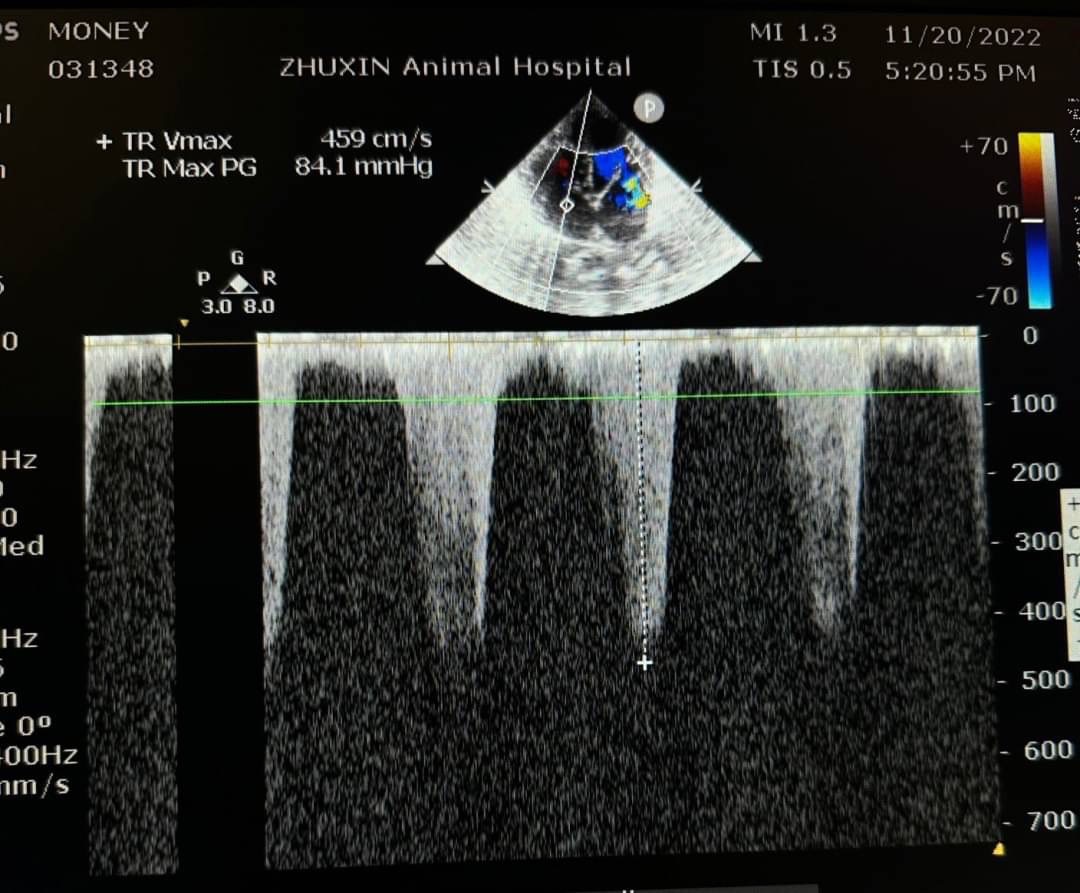

而一般常使用心臟超音波參數和結構回推肺部壓力是否過大

如測量肺動脈或是三尖瓣逆流的流數,心臟結構的改變,如右心房擴張、右心室肥厚、收縮期中隔平坦、肺動脈擴張(PA:AO >1)等。